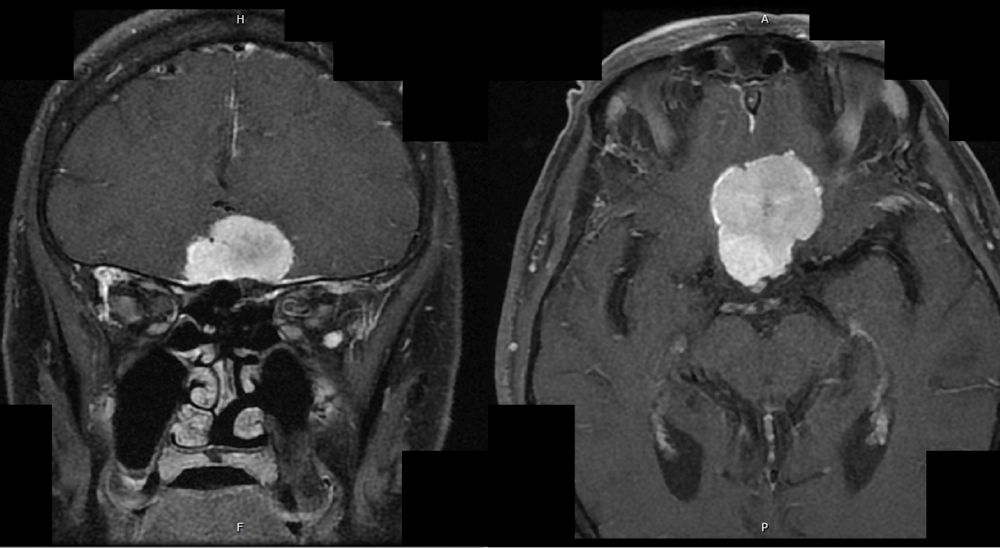

An MRI of the brain with gadolinium contrast was obtained and the results are shown here.